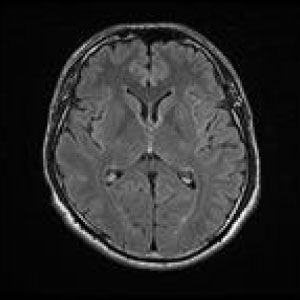

MRIはMagneticResonanceImageの略で強い磁石と電波によって人体の構造を見ることが出来る検査です。

頭部領域から脊椎・関節・骨疾患、腹部に至るまで全身部位の診断に役立ちます。

脳梗塞、脳腫瘍、脳動脈瘤、頚髄症、椎間板ヘルニア、脊柱管狭窄症、脊椎圧迫骨折、腱板損傷、各関節靭帯損傷、半月板損傷、骨壊死、肉離れ、骨腫瘍、軟部腫瘍、炎症、など

心臓ペースメーカー、脳動脈クリップ、人工心臓弁、血管ステント、など体内金属がある方など検査ができない場合があります。詳しくは当院スタッフにお問い合わせください。